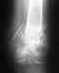

Прикладываю снимок от 31 августа.

• Кликните для загрузки файла DSC06357.JPG

234KB (240534 bytes)

Похоже, есть смысл не ждать, а переделать.